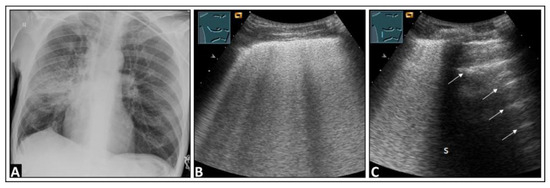

4. Pulmonary Edema and Acute Respiratory Distress Syndrome